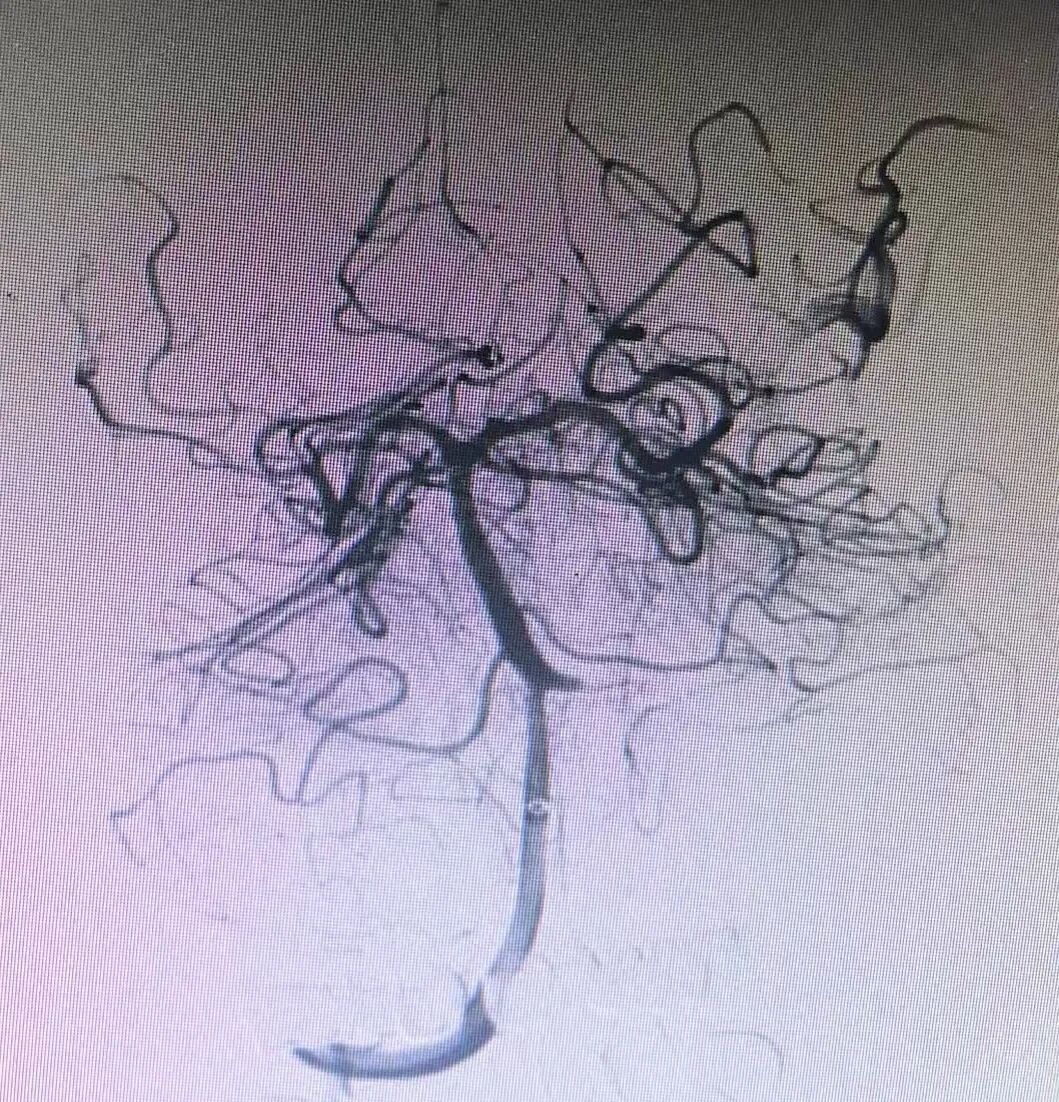

手术室内,神经介入团队沉着应战,凭借丰富的临床经验与娴熟的操作技巧,经股动脉穿刺,精准置入导管,在数字减影血管造影(DSA)的实时引导下,穿过复杂的血管通路,直达闭塞部位。面对黏连紧密的血栓,团队精准操控取栓支架,精准抓取、缓慢回撤,一气呵成成功取出血栓。造影影像清晰显示,闭塞的基底动脉即刻复通,脑部供血迅速恢复,手术全程两小时,为患者后续康复筑牢了关键基础。